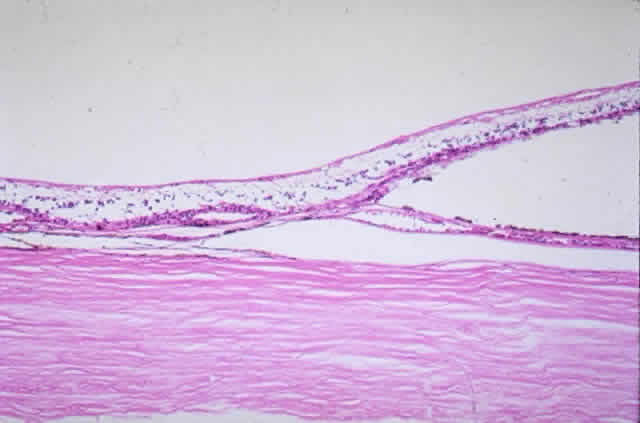

in a healthy globe.17–20 Drusen, ophthalmoscopically visible deposits present between the RPE basement

membrane and the inner collagenous layer of Bruch's membrane, are

membrane thickness.  Fig. 9. Solitary nodular drusen (arrow) resting on inner surface of Bruch's membrane. (H & E, × 63) Fig. 9. Solitary nodular drusen (arrow) resting on inner surface of Bruch's membrane. (H & E, × 63)